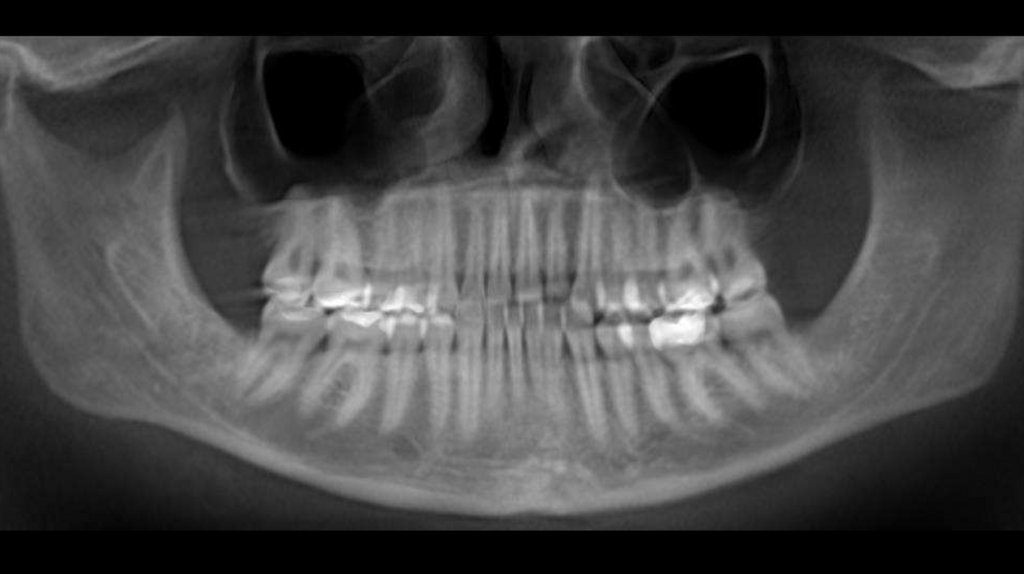

Дентальный: II по молярам справа и слева, по клыкам

справа I, слева II, сужение верхнего зубного ряда,

обратная окклюзия (перекрест) в области 12 46 35,

трансверзальная резцовая окклюзия на 3-3.5 мм влево

взр, трансверзальная резцовая окклюзия на 1 мм вправо,

мезиализация 46, 47, 26, 27 . Тортоаномалия 12, 24, 25,

35.

Скелетный: II класс.